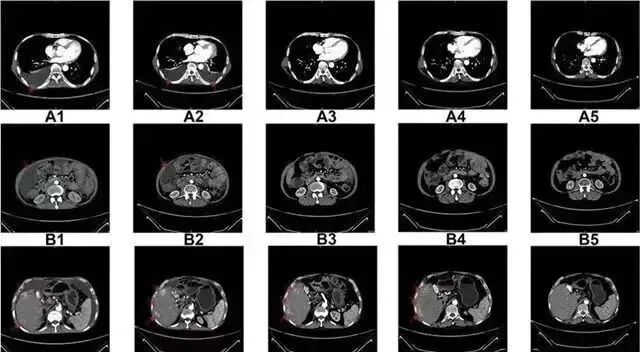

△  NK细胞治疗前和治疗期间的CT扫描结果

案例2:国内一名60岁的卵巢癌晚期患者,在接受了体外扩增,高度活化的同种异体NK细胞的治疗后,CA125水平从11,270降至580,所有腹水都消失了。此外,CT扫描的肿块体积减小,并且没有出现副作用。

案例3一名广泛期小细胞肺癌患者,在进行4个疗程化疗和4次高度活化NK细胞回输后,患者第一次进行治疗后的CT复查,结果显示,肿瘤缩小到了原来的1/8。而且距发病第六年的CT复查中,仍旧没有发现任何异常及复发的迹象。